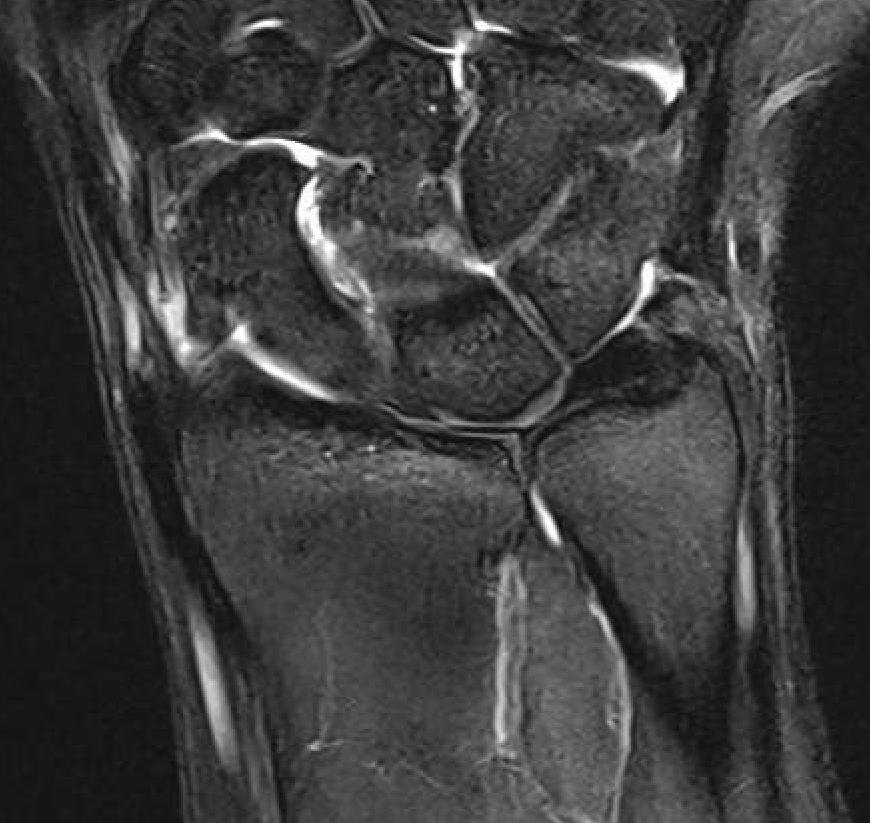

TFCC tears

Ulna sided tear

Radial sided TFCC tear

Central TFCC tear

Ulno-carpal abutment

Ulnocarpal abutment and lunate chondromalacia

Central TFCC tear with ulna positive variance an ulnocarpal abutment on MRI